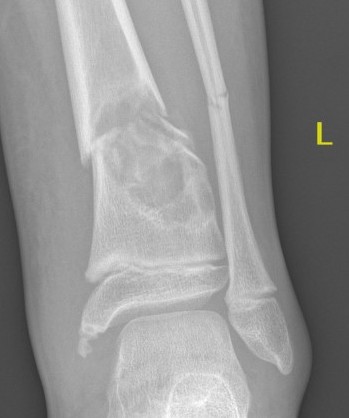

Can occur in calcaneum

X-ray

Well-defined lucency

- thin sclerotic rim

- usually central

- thinned cortex with slight expansion

- thin internal septa

- can be multi-loculated

Fallen-Leaf (AKA fallen-fragment)

- with pathological fracture

- indicates that the lesion has no matrix and is fluid filled

Fallen leaf sign

DDx ABC